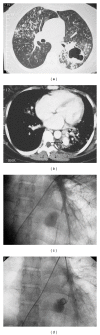

Massive hemoptysis is a life-threatening medical emergency. Prompt radiological diagnosis and management are essential. I present a case of an inflammatory pulmonary aneurysm (Rasmussen aneurysm) from active pulmonary tuberculosis. This is an uncommon cause for massive hemoptysis which was successfully treated by endovascular coiling.